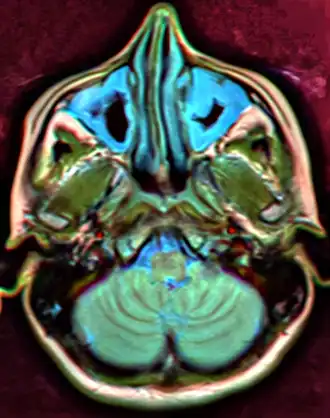

MRI image showing sinusitis. Edema and mucosal thickening appear in both maxillary sinuses. -